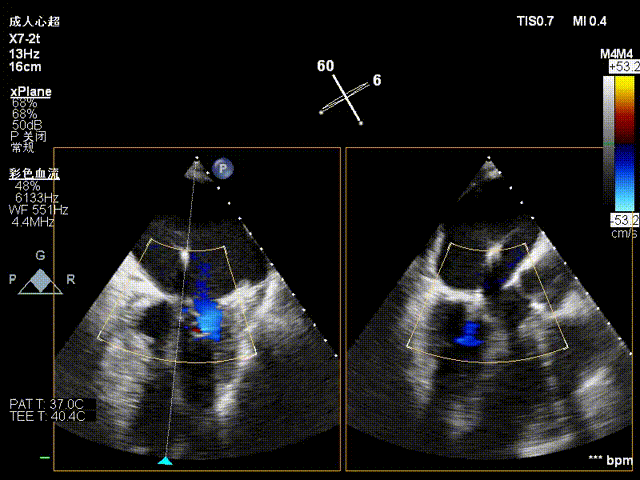

术前影像

手术难点/病例特征

该病例为二尖瓣重度反流,前叶A3区瓣叶脱垂并并腱索断裂,后叶瓣叶合并钙化,捕获瓣叶有一定难度。拟植入一枚NeoNova®C6(宽6mm)夹合器于3区脱垂处解决主要脱垂,然后根据残余反流和瓣口面积条件判断是否需要植入第二枚夹合器。